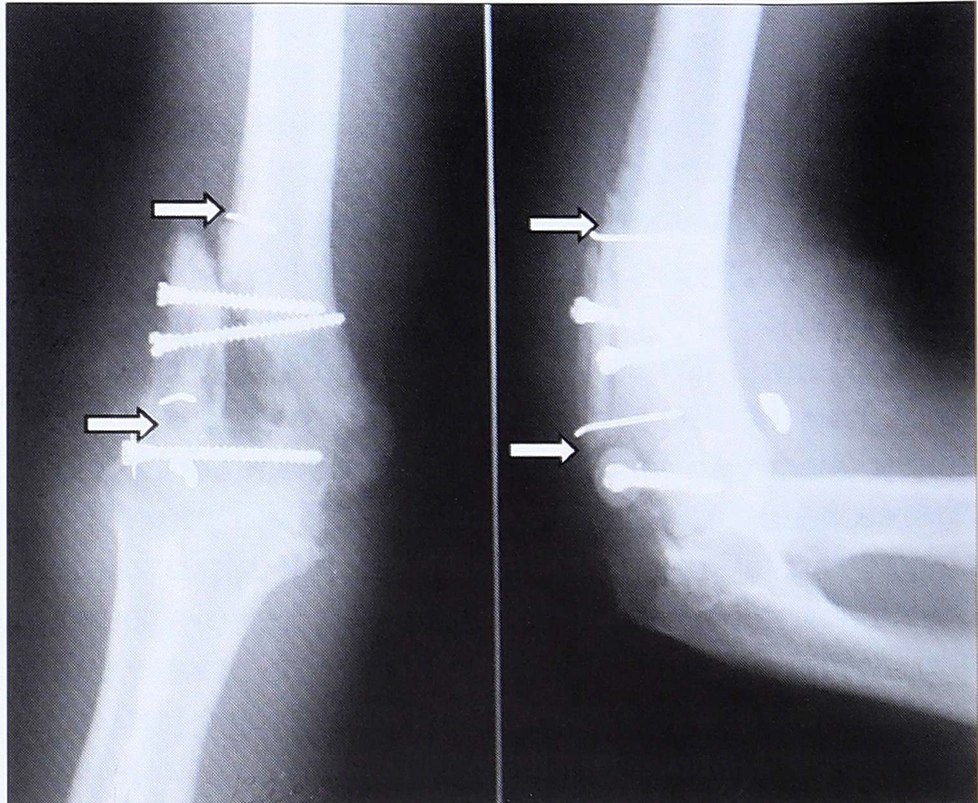

20.01.00 пациент оперирован. Первым этапом локтевой нерв выделен из рубцовых тканей. Затем задним доступом, с рассечением сухожилия трехглавой мышцы плеча произведено выделение костных фрагментов с мобилизацией фрагмента латерального надмыщелка и головочки надмыщелка плечевой кости. При этом скелетированный фрагмент высвобожден из грубых рубцовых тканей. Выполнен остеосинтез фрагментов компрессирующими винтами с созданием конгруэнтной суставной поверхности (рис. 2, а, б). Соприкосновение отломка с плечевой костью достигнуто лишь в дистальной и проксимальной частях отломка из-за дефекта костной ткани.

Рис. 2. В процессе операции (тот же больной К.).a — смещение фрагментов головочки надмыщелка плечевой кости; б — головочка надмыщелка после остеосинтеза (дорсолатеральная и дорсальная позиции); в — выделен лучевой надкостнично-кортикальный лоскут на сосудистой ножке; г — лучевой лоскут выведен в область локтевого сустава; д — лучевой лоскут фиксирован спицами к скелетированному и репонированному костному фрагменту надмыщелка и головочки надмыщелка плечевой кости.

На контрольной рентгенограмме: локтевой сустав конгруэнтен, суставная щель прослеживается отчетливо, оси плечевой и локтевой костей совпадают (рис. 3).

Рис. 3. Тот же больной К. Рентгенограмма после операции: восстановлена конгруэнтная суставная поверхность плечевой кости.